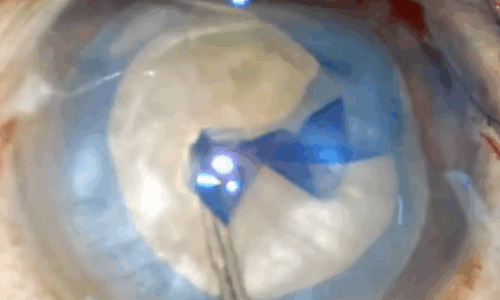

Complications et gestion des cas complexes Plus d'info...

Complications et gestion des cas complexes

2

440

students

130.00€89.00€